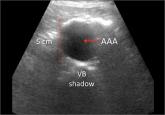

Family medicine ultrasound. Because of advances in technology and reductions in the cost of portable machines, ultrasound use is rapidly moving into family medicine offices. Drs. Steinmetz and Oleskevich provide a no-nonsense review of the current uses of ultrasound in family medicine, leading me to wonder whether ultrasound might become the stethoscope of the future.

This month’s review of the current uses of ultrasound in family medicine made me wonder whether ultrasound might become the stethoscope of the future.